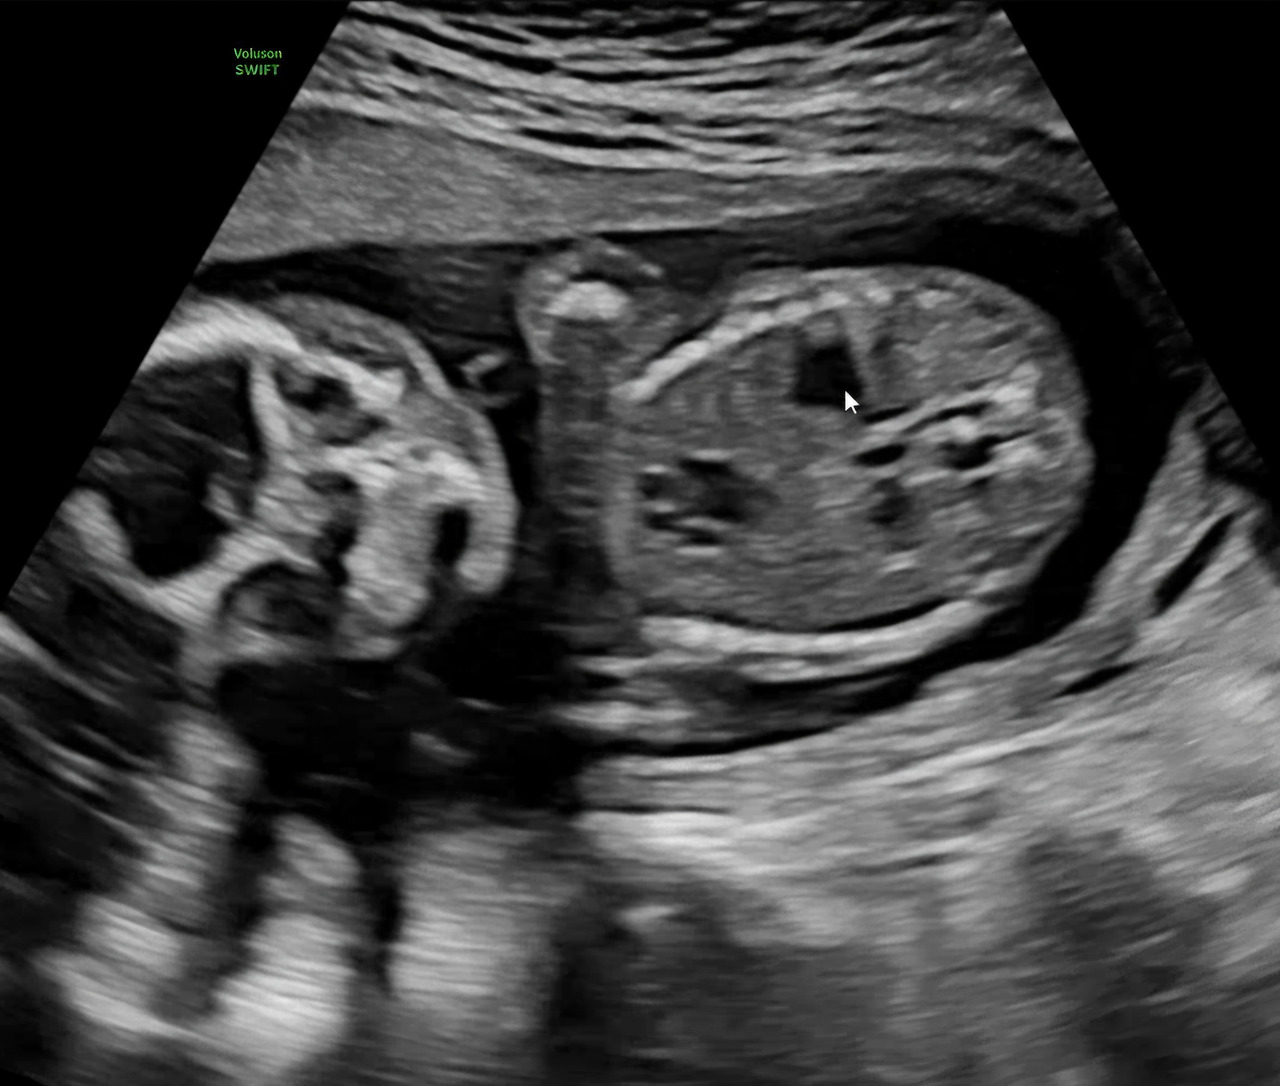

25년 10월 27일 초음파. 링링의 얼굴과 장기가 조금씩 보이는 모습.

초음파 화면 속 넌 역시나 아주 잘 놀고 있었어.

병원에 가기 직전 캐러멜 사탕을 하나 집어 먹었더니 그 달콤한 기운 때문인지 정말 쉼 없이 움직이더라.

이번엔 너의 다섯 개의 작은 손가락도, 다리 사이에 존재감을 드러내고 있는 그것(!)도 처음 봤어.

정말 귀엽고 신기했어.